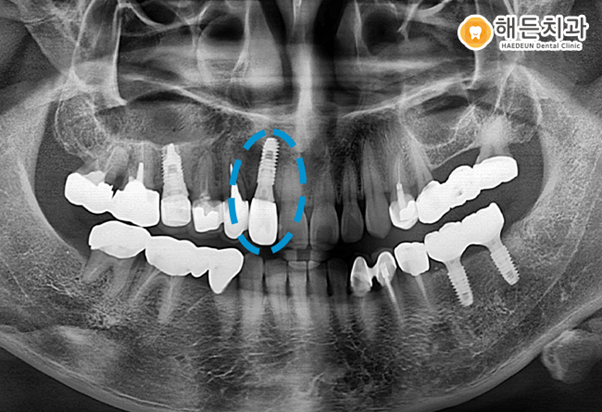

우선 사진을 보시면 임플란트의 뿌리 역할을 하는 인공치근만 심은 상태인데요.

인공치근이 뼈와 잘 유착될 수 있도록 3~4개월 정도 기다린 후 치아의 머리 역할을 하는 보철물을 씌우게 됩니다.

시멘트가 제대로 굳지도 않았는데 건물을 올리게 되면 부실공사로 인해 무너질 수가 있듯이, 임플란트도 마찬가지입니다.

충분한 시간을 기다린 후 보철물을 씌워야 임플란트의 예후가 좋습니다.